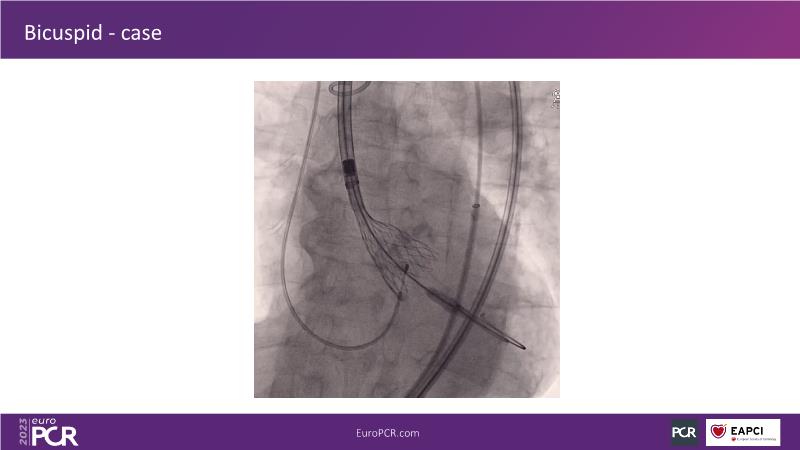

Discover the key factors to consider in selecting the optimal valve and implant technique for transcatheter aortic valve implantation (TAVI) to achieve optimal procedural outcomes. Gain insights into the impact of device choice and implantation technique on coronary access following TAVI and learn valuable strategies for tailoring your TAVI technique to complex scenarios, including bicuspid aortic valves, large and calcified anatomies, and ensuring coronary access.

- To learn how to tailor your TAVI technique to complex situations: bicuspid aortic valves, large, calcified anatomies and coronary access